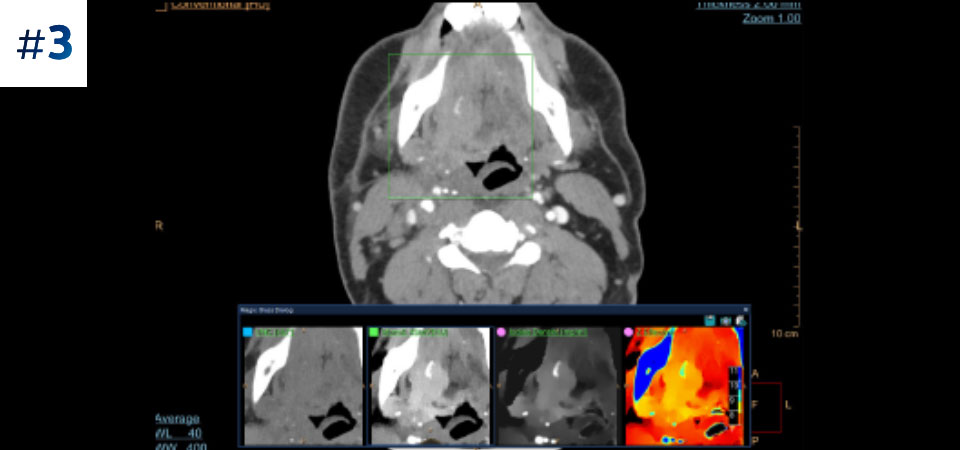

Guz szyi

Pobierz opisy przypadków tutaj

Nie ograniczaj się do konwencjonalnej tomografii komputerowej. Zobacz, jak wyniki uzyskane dzięki warstwom detektora spektralnego mogą zwiększyć pewność diagnostyczną.

Zobacz różnicę pomiędzy tomografią komputerową opartą na detektorze spektralnym a konwencjonalną tomografią komputerową